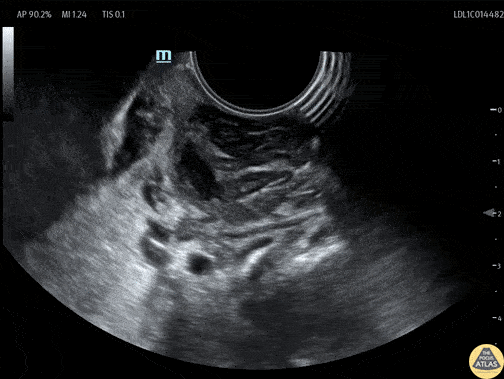

A teenaged female presented with sore throat and was noted to have asymmetric tonsillar edema on physical exam. POCUS was performed using an endocavitary probe intraorally. The findings are shown here, with edema of the tonsil and a small circumscribed area of hypoechoic fluid which has no color doppler signal. This indicates tonsillitis with a small tonsillar abscess. Given this patient’s physical exam and small size of the abscess, conservative management was recommended with oral antibiotics without incision and drainage in the ED. Dr. Cailin Frank, Fellow, Denver Health Ultrasound Fellowship